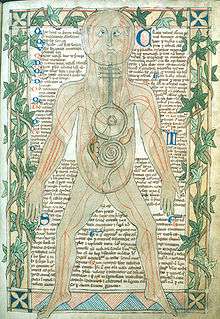

Human anatomy

Humans have the overall body plan of a mammal. Humans have a head, neck, trunk (which includes the thorax and abdomen), two arms and hands, and two legs and feet.

Generally, students of certain biological sciences, paramedics, prosthetists and orthotists, physiotherapists, occupational therapists, nurses, and medical students learn gross anatomy and microscopic anatomy from anatomical models, skeletons, textbooks, diagrams, photographs, lectures and tutorials, and in addition, medical students generally also learn gross anatomy through practical experience of dissection and inspection of cadavers. The study of microscopic anatomy (or histology) can be aided by practical experience examining histological preparations (or slides) under a microscope. [39]

Human anatomy, physiology and biochemistry are complementary basic medical sciences, which are generally taught to medical students in their first year at medical school. Human anatomy can be taught regionally or systemically; that is, respectively, studying anatomy by bodily regions such as the head and chest, or studying by specific systems, such as the nervous or respiratory systems.[2] The major anatomy textbook, Gray's Anatomy, has been reorganized from a systems format to a regional format, in line with modern teaching methods.[40][41] A thorough working knowledge of anatomy is required by physicians, especially surgeons and doctors working in some diagnostic specialties, such as histopathology and radiology. [42]